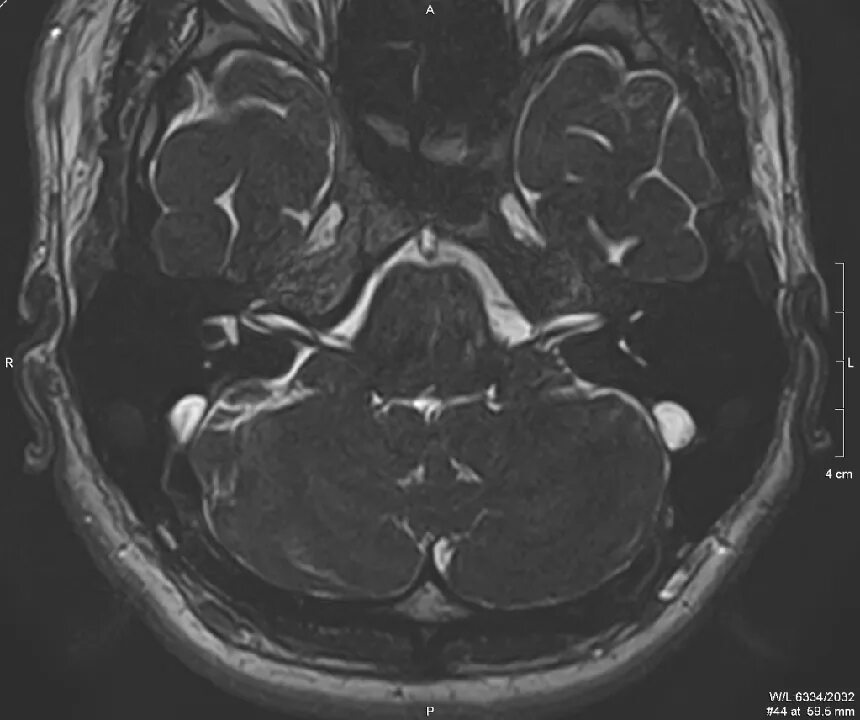

Мрт головного мозга мосто мозжечкового угла